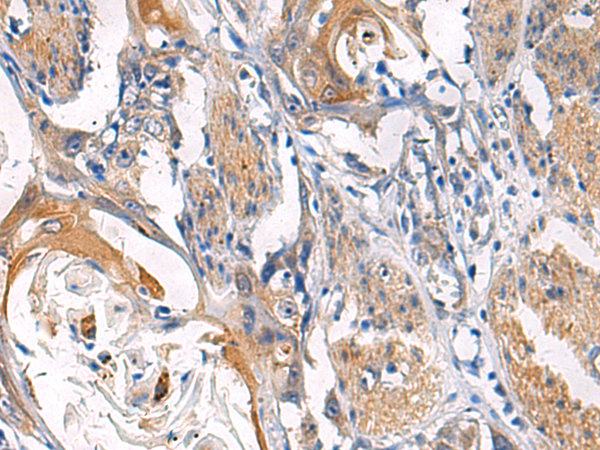

IHC positive control: |

Human esophagus cancer |

IHC Recommend dilution: |

50-200 |